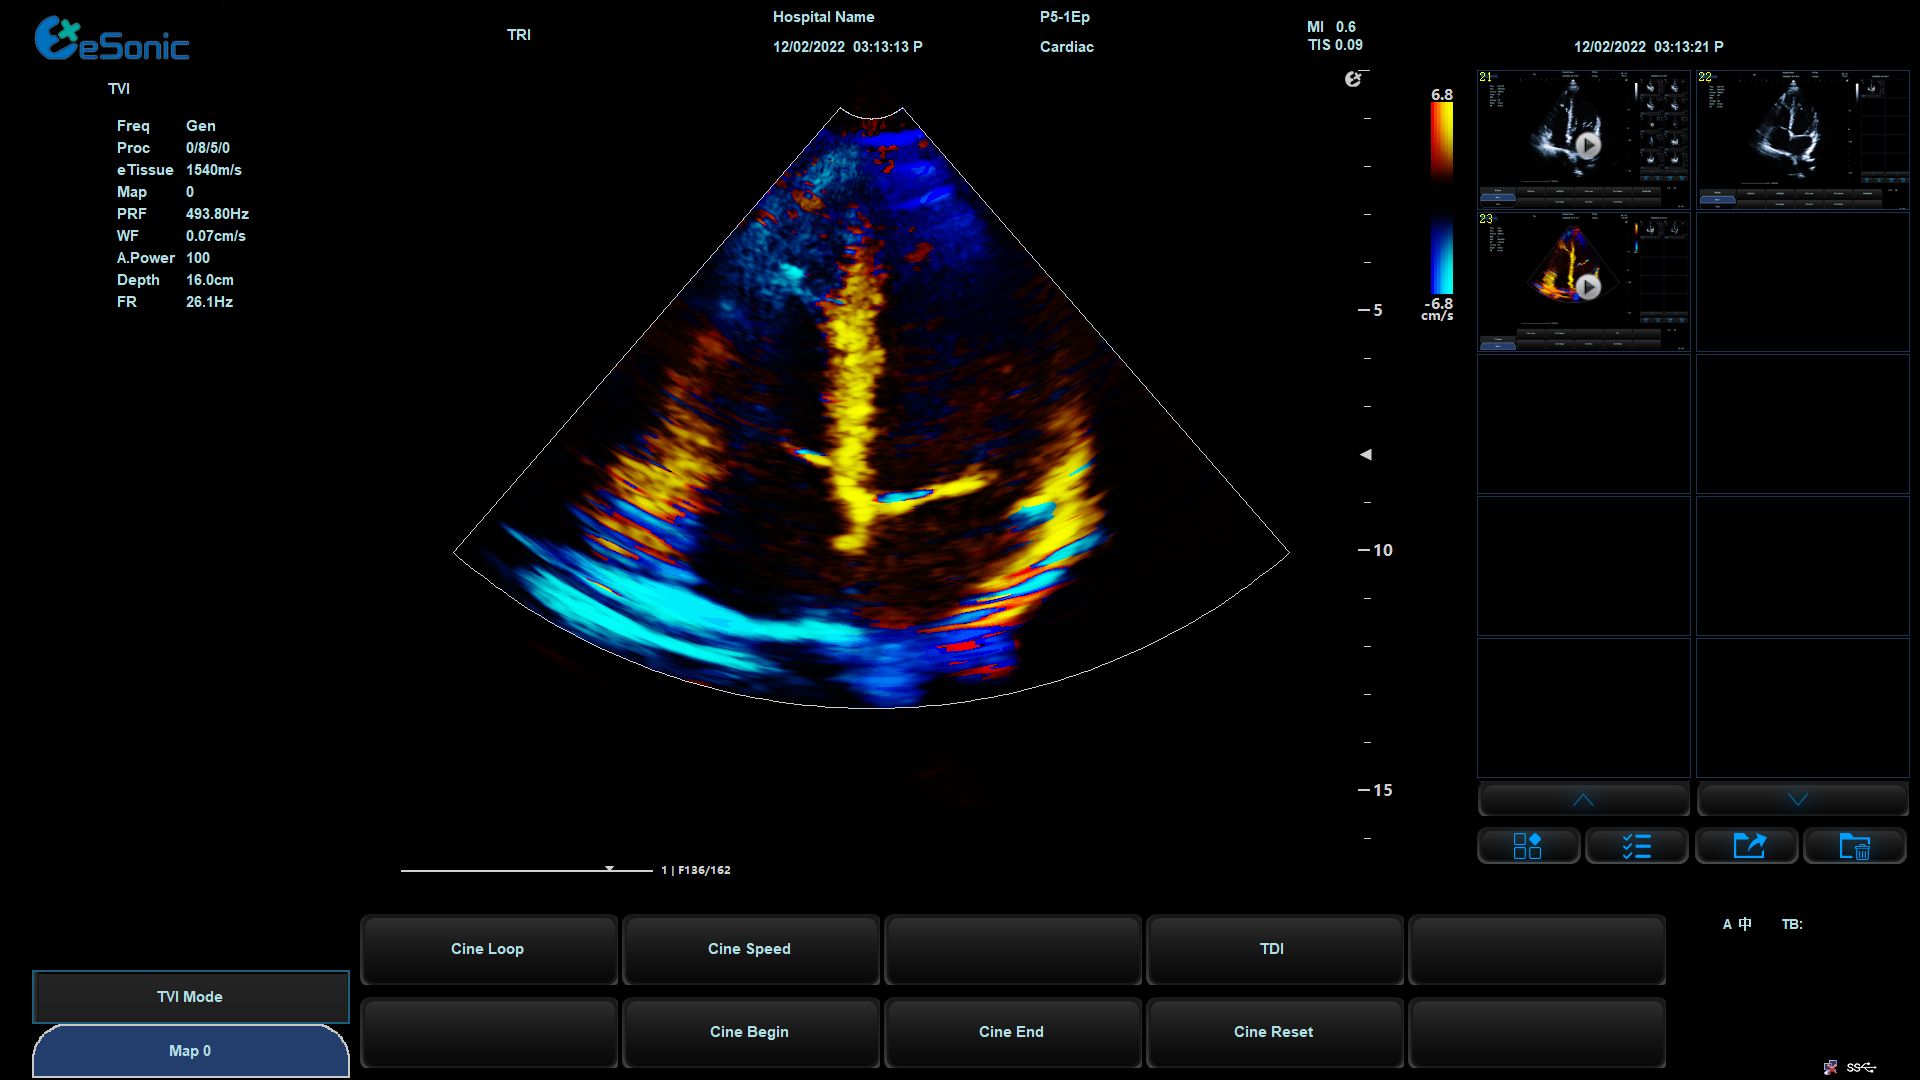

相关技术优势:eHertz的高敏感血流,提高血流敏感性,降低噪声干扰

eHertz优异的TDI表现- 图像非常干净

组织多普勒

包含多种模式

可对室壁运动进行速度、加速度的测量和分析

观察心肌运动、定量分析心肌的运动速度变化,检测心肌供血情况

评价早期的舒张功能

image.png